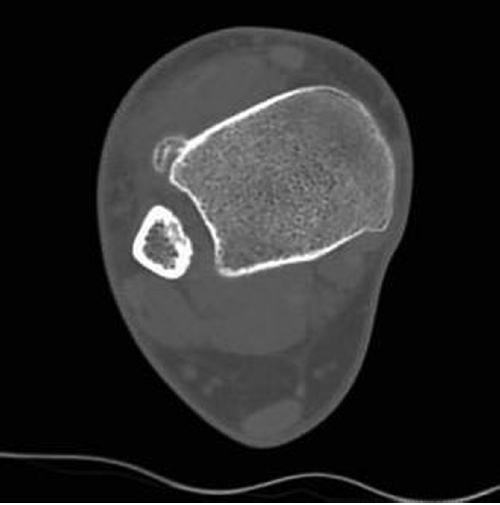

CT SCANS - CT scans provide a tridimensional radiographic view that confirms the characteristics highlighted by X-rays, adding further information about the surrounding soft tissues and the relation between the lesion and the underlying bone. CT confirms the calcific nature of the mass and excludes signs of continuity with the medullary canal or interruptions of the cortex. Moreover, it gives a better picture of the nearby soft tissues, evidencing in particular the absence of periosteal irritative reactions (Fig. 3) [3,10, 19, 64, 67].